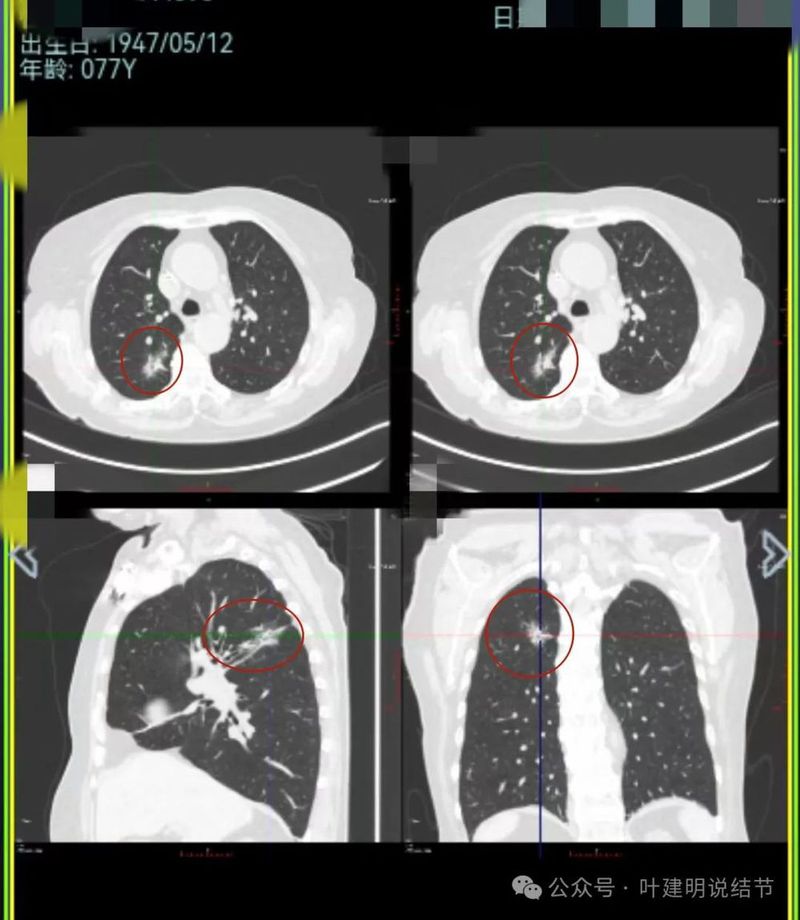

再来看2024年9月时的关键影像:

右上后段灶病灶不单没有好转,灶内密度是有增加进展的!

中叶处病灶不见了。

下叶背段伴血管征的病灶也不见了。

现在的影像考虑:

不单是右中叶以及右下叶的病灶吸收消失了,两肺其他病灶也基本上都不见了,唯独右上后段的病灶仍在而且有进展!再加上此灶原来单看也像恶性的,所以这位结友是感染与肿瘤并存,右上病灶基本上肯定是恶性的,而且是浸润性腺癌。

上图显示冠状位与矢状位形态。其实已经不重要,本来就已经基本可断定是恶性的了。